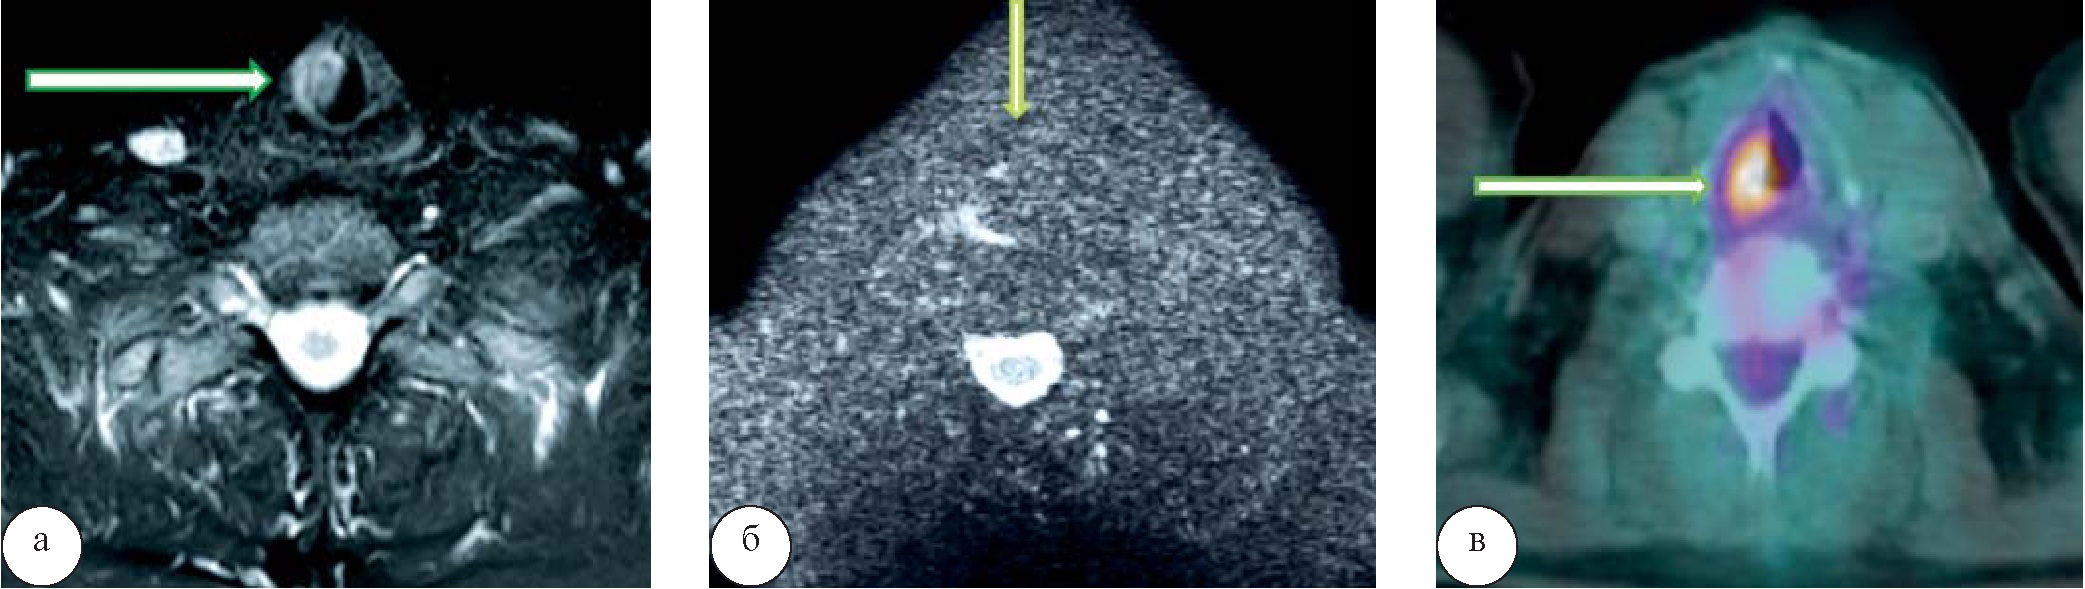

В третьей группе у 2 (3,7%) человек также в области выявленной опухоли, изоинтенсивной на ДВИ, прослеживался гиперметаболизм глюкозы (SUVmax 15,7) без сопутствующей лимфоаденопатии (рис. 6). Еще у 2 (3,7 %) пациентов в этой группе гиперфиксации РФП в области образования повышения сигнала на ДВИ не отмечалось, что было расценено как доброкачественные образования с последующей гистологической верификацией опухолей – фиброма и гемангиома (рис. 7).

Рис. 6. Рак голосовой связки. При МРТ на Т2-ВИ (а) отмечается образование правой голосовой складки, характеризующееся неоднородным гиперинтенсивным сигналом, изоинтенсивное при МР-диффузии, без повышения сигнала на b=800 (б). Однако при выполнении ПЭТ/КТ (в) в области образования правой голосовой складки определяется гиперметаболизм 18-ФДГ